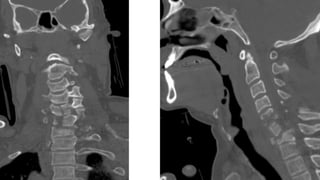

COLUMNA CERVICAL

• Una serie adecuada incluye:

• Proyección lateral de columnacervical con

rayo horizontal

• Deben visualizarse:

• Base de cráneo

• 7 vértebras cervicales.Valorar tracción de

hombros.

• 1ª vértebra torácica si es posible

• AP

• Proyección de odontoidescon boca abierta

• Sin movilizar al paciente

PARTES BLANDAS

• Valorar hematoma por FX

valorar espacios:

• E. Nasofaríngeo (C1)=10mm

• E. Retrofaríngeo (C2-C4)= 5-7mm

• Retrotraqueal (C5-C7)= 22mm ó

(< 1 cuerpo vertebral).

Nasofaríngeo

Retrofaríngeo

Retrotraqueal